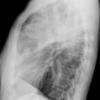

Case 3 RM & UL pneum Lat

Date: 07/04/2004

Views: 7242